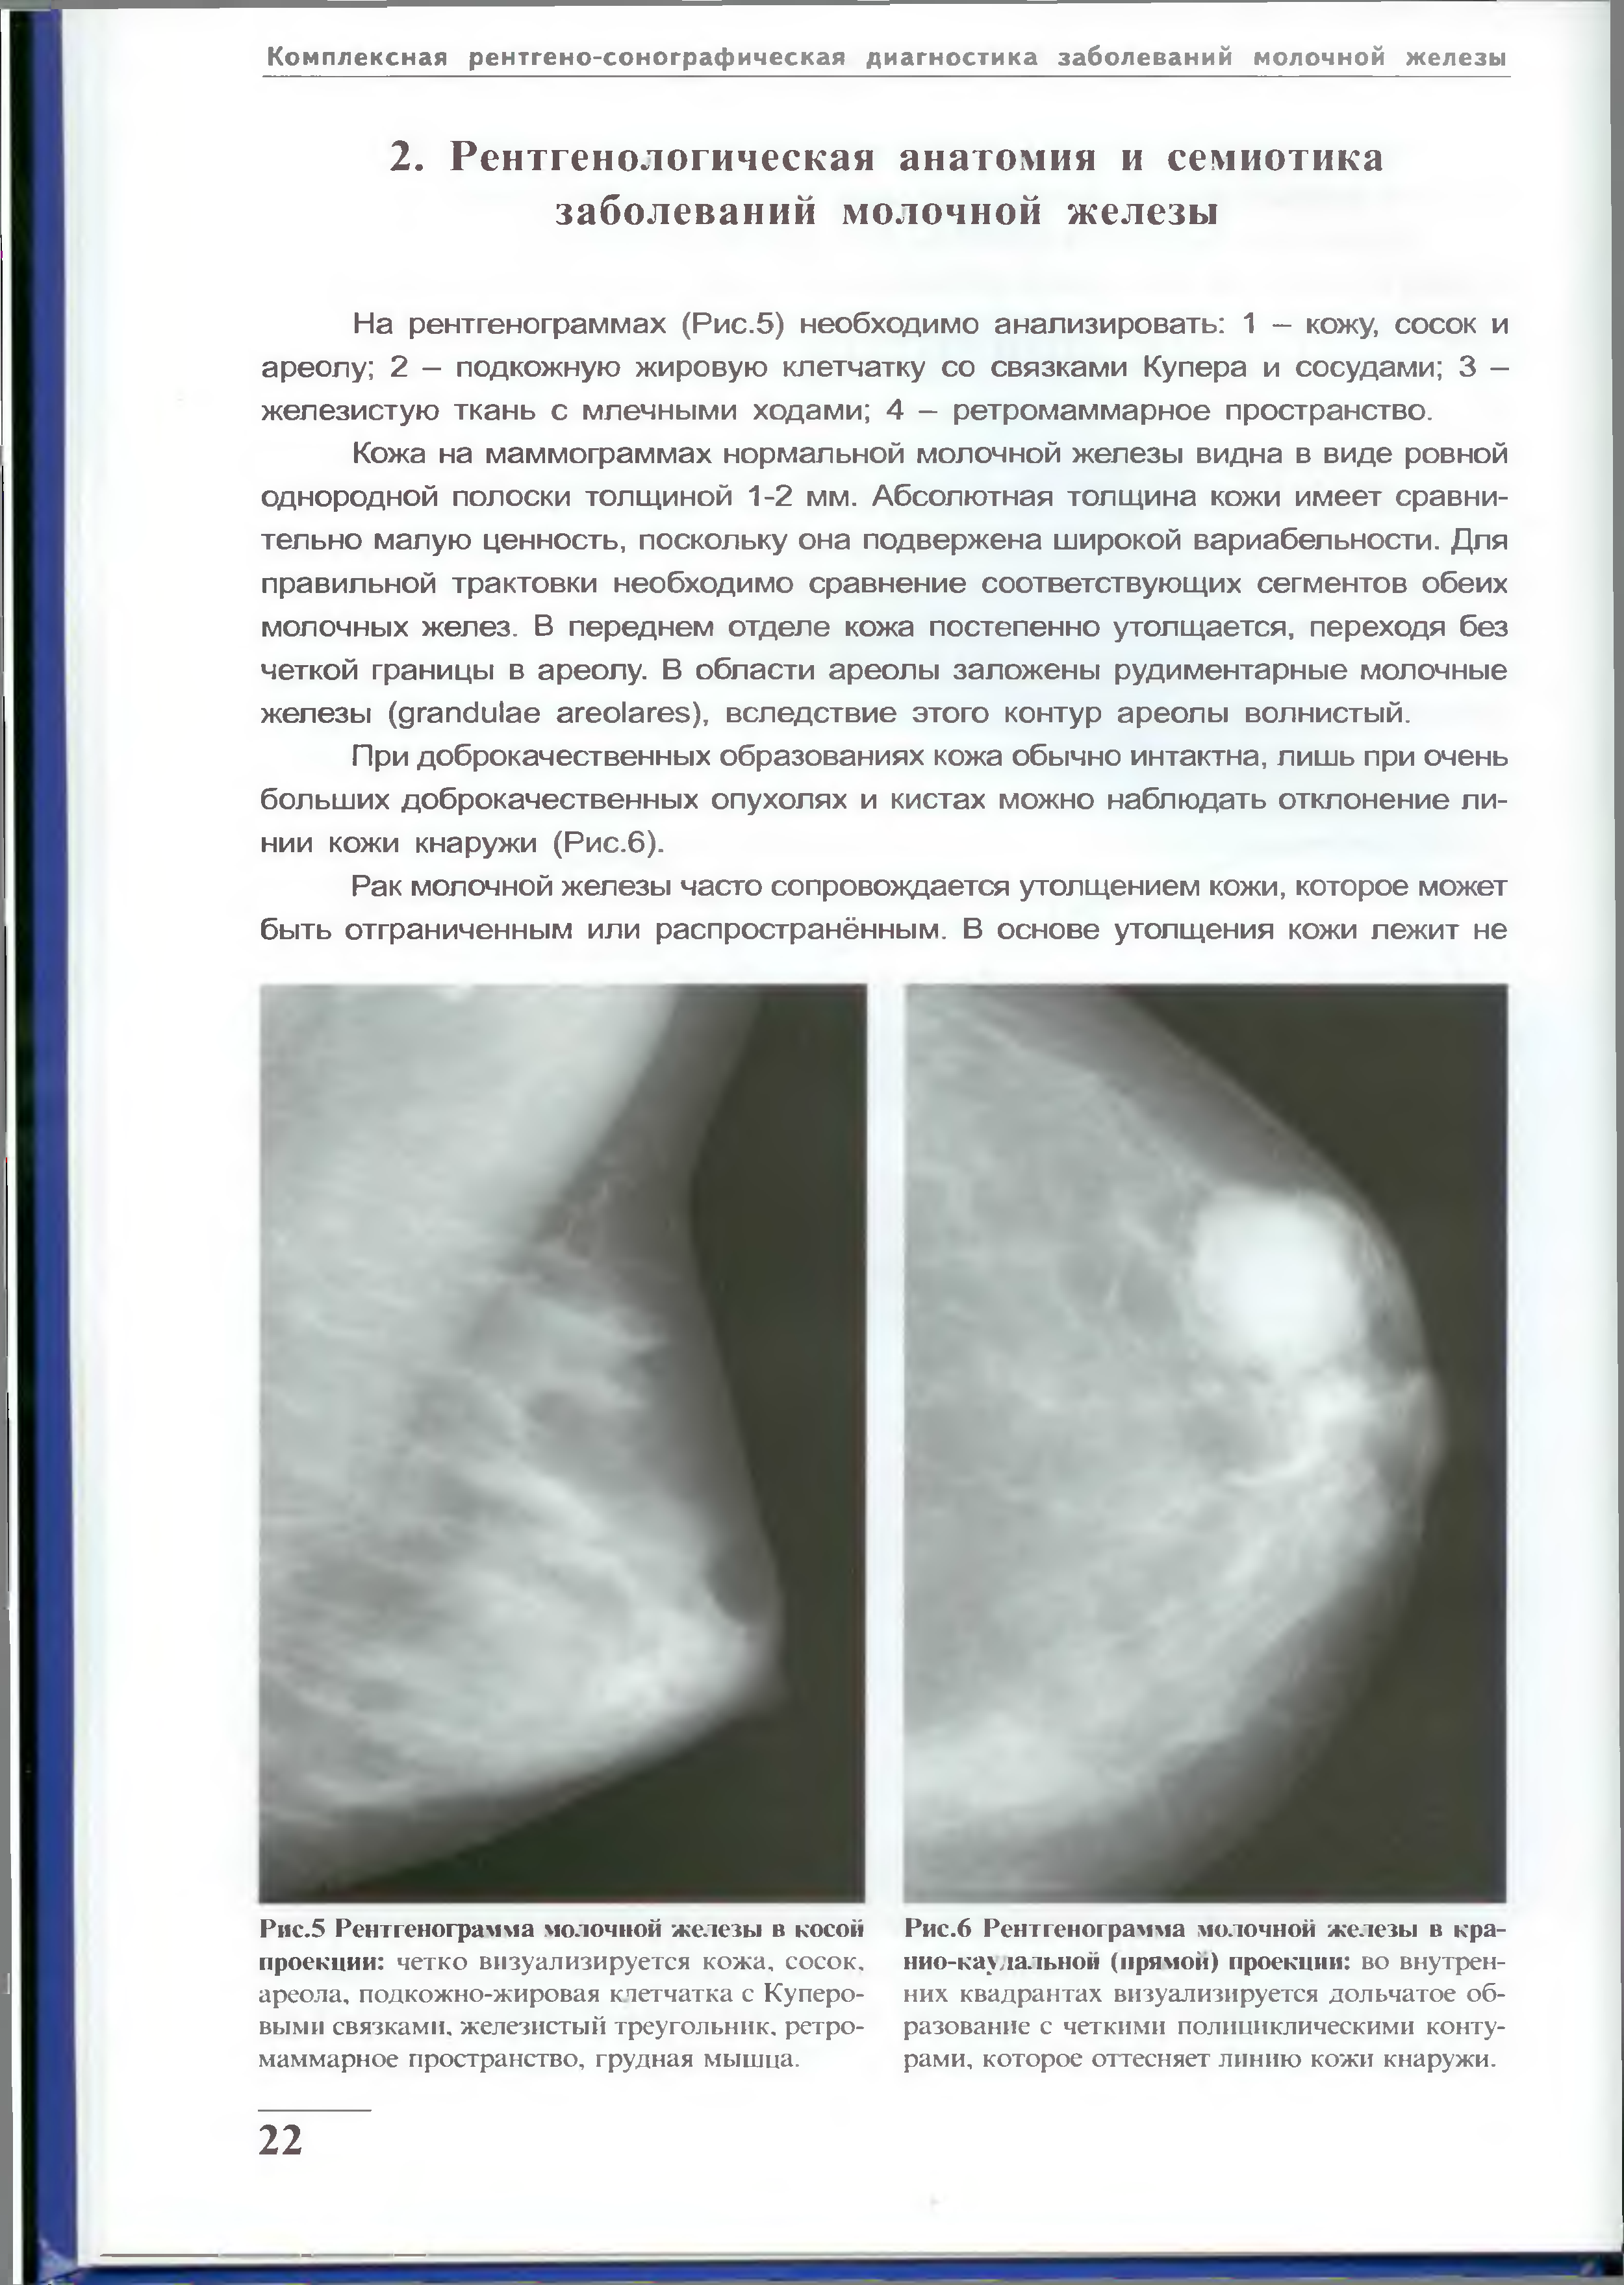

Маммография и ее роль в диагностике фиброаденомы молочной железы

Маммография - это рентгенологическое исследование молочных желез. Оно позволяет выявить различные изменения в тканях, включая фиброаденому. На маммограммах можно увидеть структурные особенности опухоли и отследить ее динамику во времени.